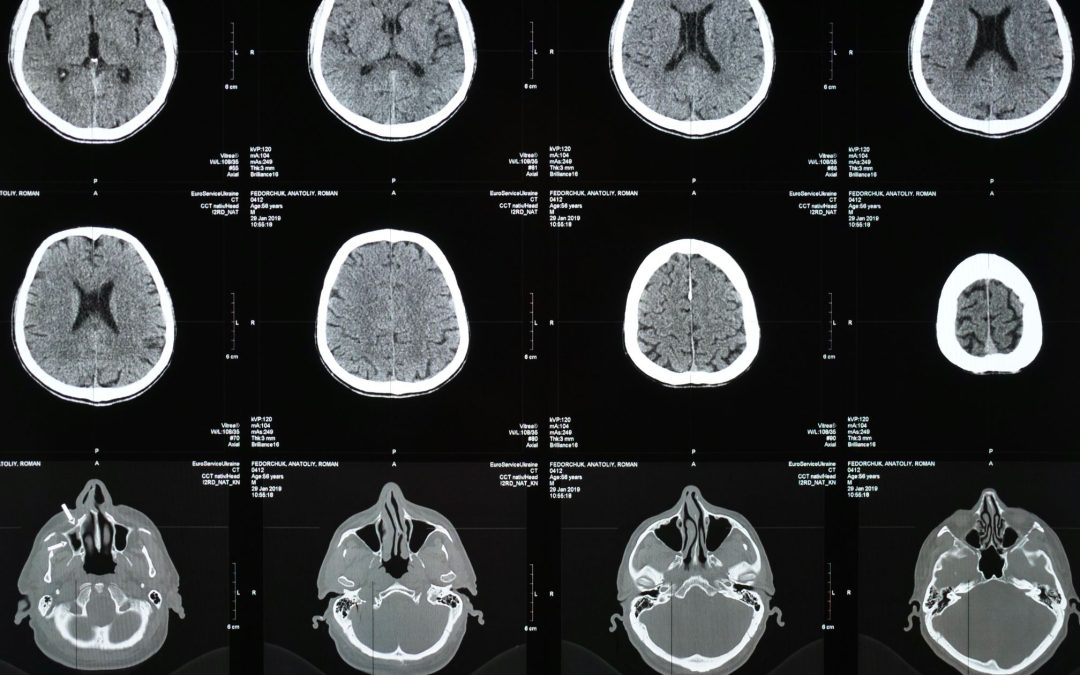

Técnicas de diagnóstico por imagen: especialidades y aplicaciones clínicas

Autora: Dra. Claudia Martínez Higueros La radiología médica ha evolucionado de forma extraordinaria desde sus orígenes a finales del siglo XIX. Hoy en día, no se trata de una única disciplina, sino de un conjunto de subespecialidades clínicas y técnicas de imagen que...